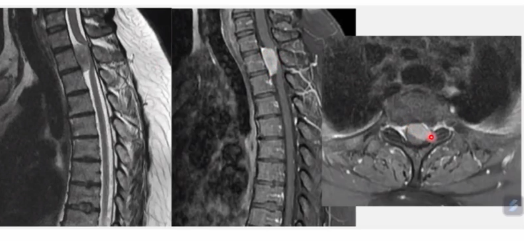

Ependimoma Medular

Características de imagem

Central ou LAteral?

Simétrico ou assimétrico

Impregnação de contraste?

É comum seringomielia?

É comum haver calcificação?

A

Centromedular

Simétrico

Impregnação heterogênea

Seringomielia (65% dos casos)

Pode haver calcificação

Pode ser circunscrito ou infiltrativo